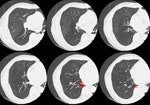

A CT scan of the chest was performed and revealed decreased attenuation

within the right middle and lower lobes, with a decreased number of vascular

markings. Bronchiectatic changes were also noted in the right lower lobe

(red arrows). Bronchoscopy was negative, and the findings were felt to

most likely be related to a lobar Swyer-James syndrome.